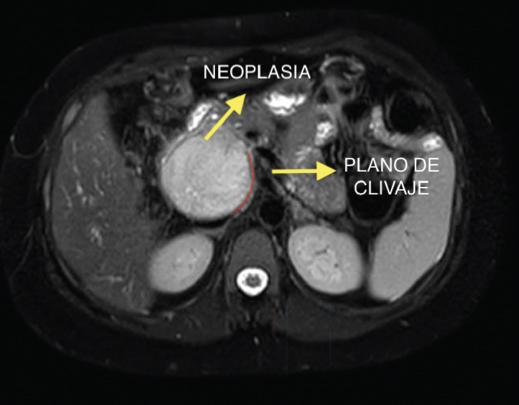

Mujer de 33 años sin antecedentes, estudiada por epigastralgia, diarreas, saciedad precoz y distensión abdominal. Se realiza una analítica que reporta marcadores tumores normales. La tomografía computarizada (TC) (Fig. 1) multifásica con contraste y la resonancia magnética (RM) (Fig. 2) evidencian una lesión a nivel de la cabeza-proceso uncinado del páncreas, hipointensa en T1 e hipertensa en T2, de diámetro mayor de 92 mm, sin asociar dilatación de la vía biliar, atrofia distal glandular ni lesiones a distancia. Se sospecha una neoplasia pseudopapilar sólida del páncreas. Es intervenida quirúrgicamente y se evidencia una gran tumoración, cuya enucleación se desestimó por afectación de la papila duodenal, llevándose a cabo una duodenopancreatectomía cefálica de Whipple (Fig. 3). El estudio anatomopatológico confirmó la resección con márgenes sin invasión ganglionar, vascular ni perineural. La paciente completó el posoperatorio sin incidencias y fue dada de alta al noveno día. Tras 18 meses de seguimiento, persiste libre de enfermedad.

La neoplasia sólida pseudopapilar del páncreas afecta preferentemente a mujeres jóvenes. Alcanza una incidencia del 2% según algunas series. En general es asintomática y se detecta por síntomas relacionados con la compresión de órganos vecinos. Suele localizarse en el cuerpo-cola del páncreas6,7. Tiene una apariencia típica en las pruebas de imagen (TC y RM); en la RM en fase T2 se muestra como una masa hiperintensa rodeada de una pseudocápsula.